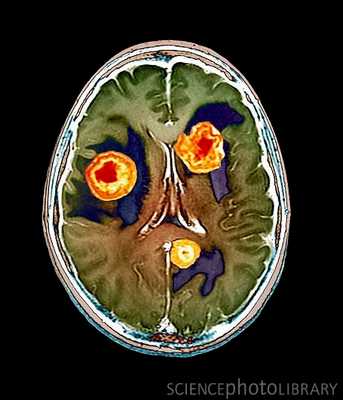

МРТ головного мозга. Т2-взвешенная аксиальная томограмма. Арахноидальная киста. Цветовая обработка изображения.

МРТ головного мозга. Арахноидальная киста полюса левой височной доли. Цветовая обработка.